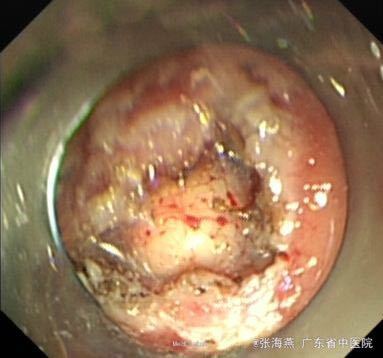

诊断:1.胃底间质瘤(ESD术后);2、慢性胃炎;3、高血压病2级;4、颈椎退行性变。 治疗:治疗上,行ESD术切除胃底肿物,术后予明可欣静滴预防感染,潘妥洛克静滴抑酸护胃,铝镁加混悬液口服保护胃粘膜,以及补液营养支持治疗。术后病理提示:符合胃肠道间质瘤(低级别,无风险);经治疗后,患者无特殊不适,予出院。

随访:ESD术后3月随访,患者无上腹部疼痛发作。 讨论:患者胃底间质瘤已完整切除,属低级别、无风险,就无需服用格列卫,嘱患者定期复查胃镜。